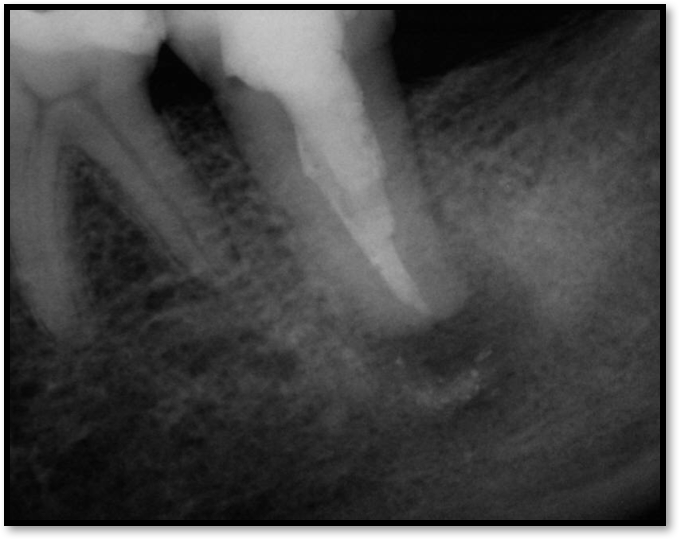

Figure 2 shows a situation where the clinician excavated the tooth of a patient with decay, and it pulped out. The buccal and lingual walls were intact; however, the walls were minimal, and there were still fragments of amalgam and cracks. If the clinician prepared this tooth after building it up, the clinician would lose all the good tooth structure that was left. This tooth would likely need a post.

Fig 2. Minimal walls.

Figure 2